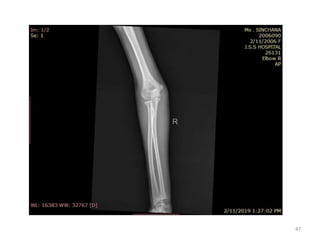

Elbow joint

• Secondary ossification Centres : (3 bones; 6 Ocs)

Capitulum (C) - appearance - 1 year of life

Head of Radius (R)– appearance -4 to 5 years

Medial Epicondyle (ME)

Appearance – 5 to 6 years

Fusion – 16 to 17 years

Trochlea (T) – appearance – 9 to 11 years

Olecranon Process of Ulna (OP)

Appearance - 8 to 9 years

Fusion- 16-17 years

Lateral Epicondyle(LE) – 11 to 12 years

Conjoint (Composite)Epiphysis (CE) [fusion of C+T+LE]

Formation – 14 to 16 years

Fusion – 16-17 years

Note: Fusion of O.Centres at elbow joint is 16-17 years in male, 15-16 years in female